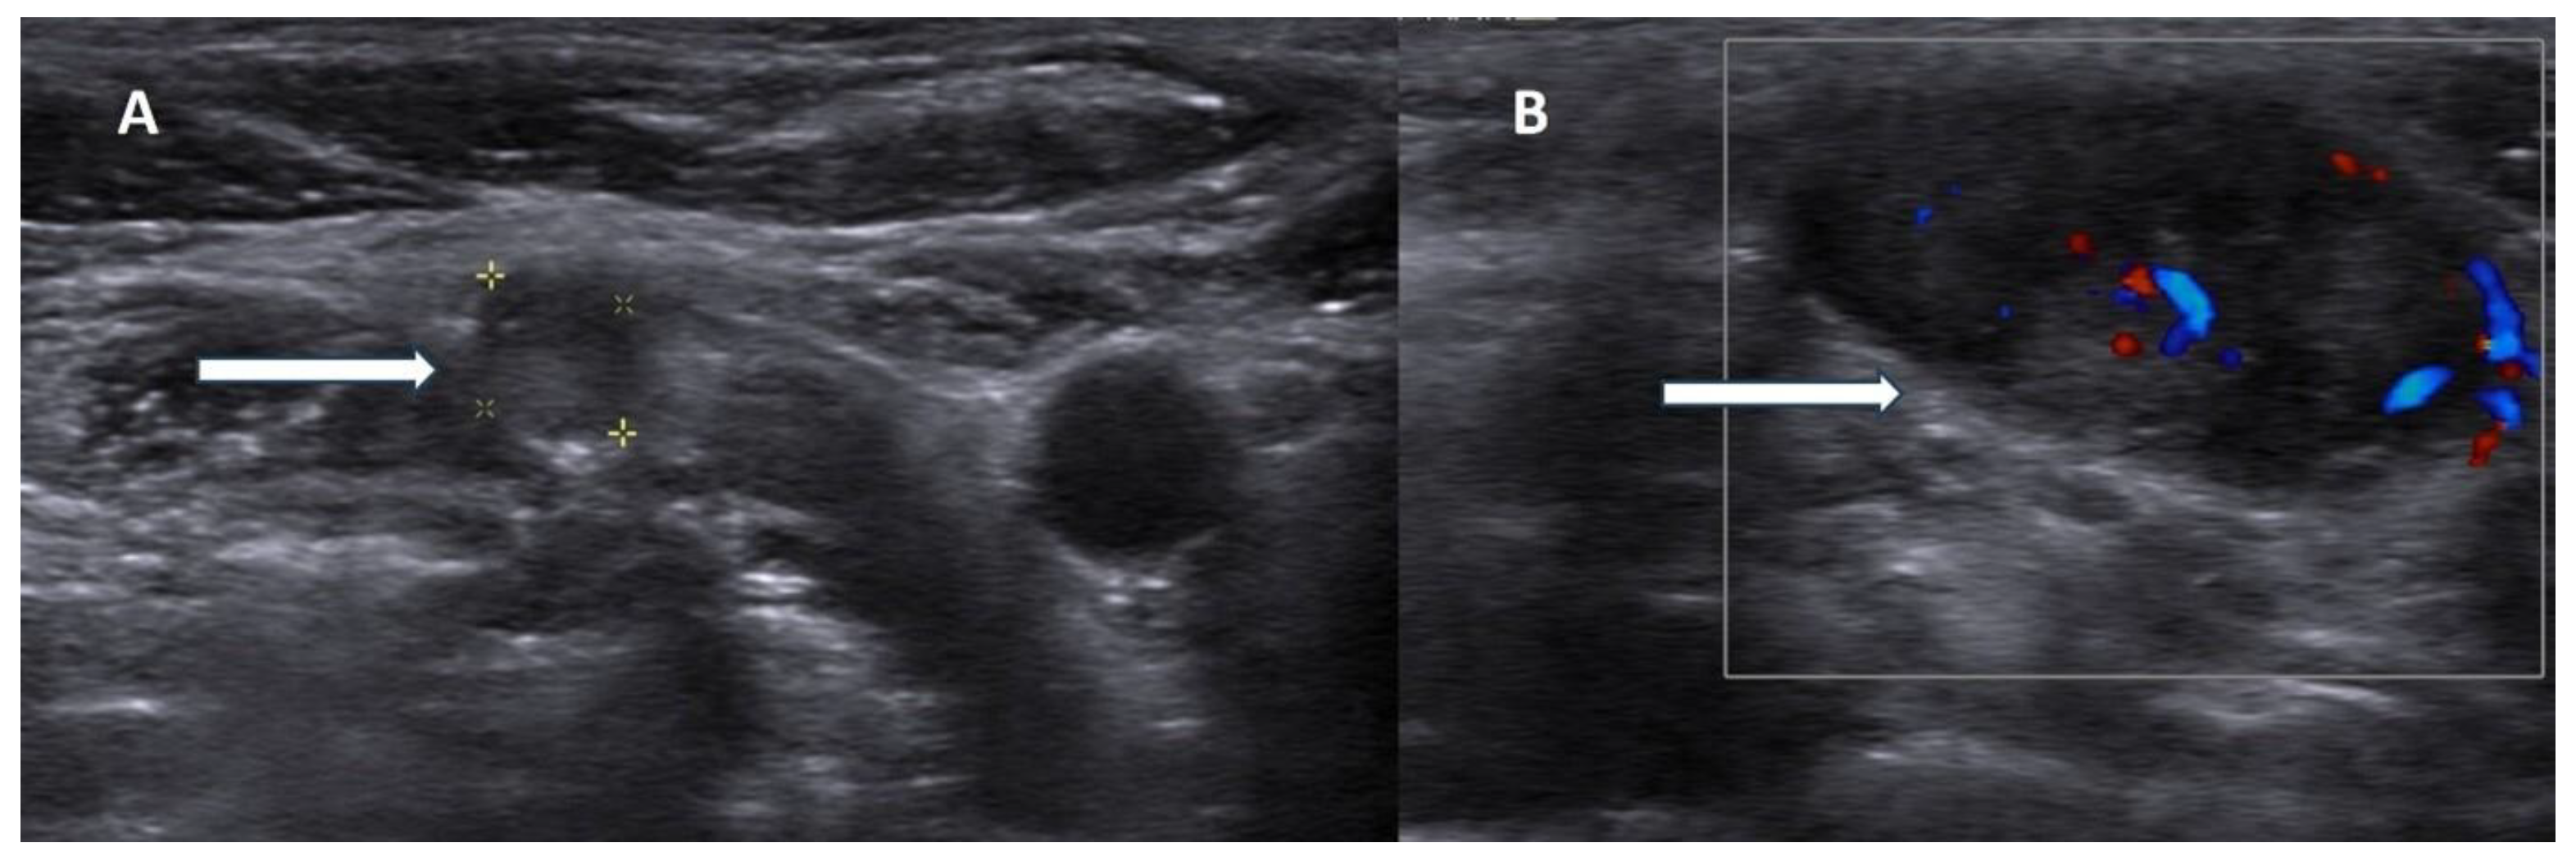

Recent technological advances have improved the diagnostic performance of US through detective flow imaging, a novel technique that surpasses traditional color Doppler in detecting slow microvascular blood flow. A 2024 study by Matsui et al. highlights its clinical utility, demonstrating successful visualization of low-velocity flow patterns within parathyroid tumors. This method enabled the detection of vascular-rich PC and provided valuable insights into lesion microvascularity, thereby enhancing diagnostic confidence in differentiating PC from benign disease [18].

While detective flow imaging offers a promising non-invasive advancement in enhancing the diagnostic accuracy of US, several important limitations must be acknowledged. The method requires dedicated high-performance equipment and operators with specialized training, which may restrict its availability to expert centers. Furthermore, larger prospective validation studies are needed to define standardized diagnostic criteria, establish sensitivity and specificity for malignancy detection, and ensure reproducibility across institutions.